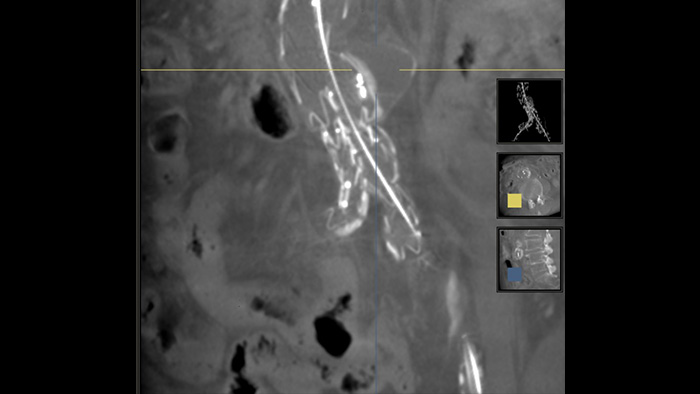

SmartCT Soft Tissue

SmartCT SoftTissue - CT-like visualisation of soft tissue, bone and vascular structures

Get step-by-step guidance to simplify CBCT acquisition

Interact with your CBCT image at table side

Access advanced 3D measurements at table side

SmartCT Soft Tissue is an X-ray acquisition technique that generates a CT-like visualisation of soft tissue in relation to other structures during procedures – all controlled via the touch screen at the table. You can use the CT-like images to assess soft tissue, bone structure and stent deployment before, during and after interventional procedures. This technique is particularly useful to check for complications after (complex) EVAR procedures.